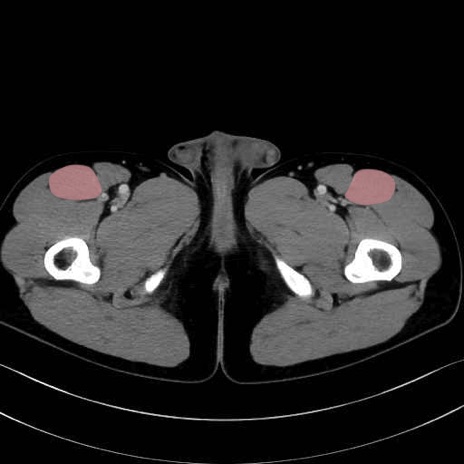

大腿直筋 (Rectus femoris)